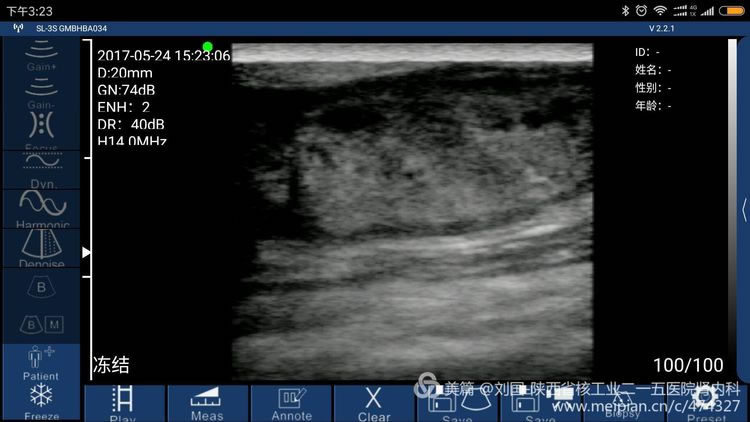

索诺星无线超声检查的头静脉情况,显示器是我的小米max。